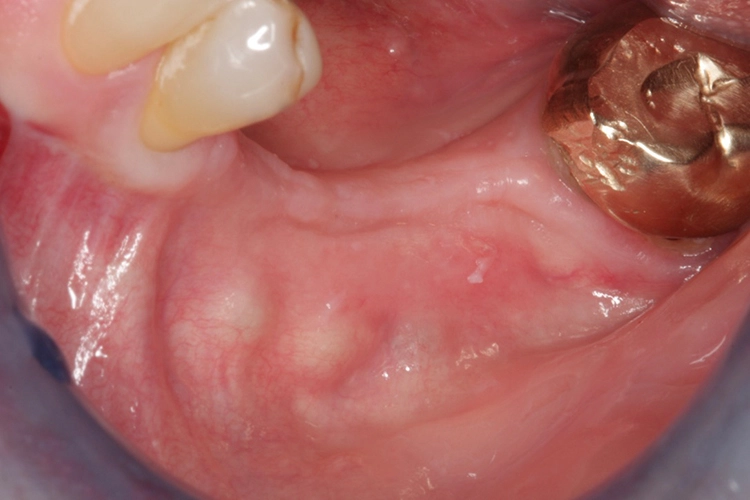

Die Wiedereröffnung des Operationsgebietes erfolgte nach vier Monaten. Länger sollte nicht mit dem Re-entry gewartet werden. Es zeigte sich, dass nur wenig keratinisierte Schleimhaut am Tag der Freilegungsoperation vorhanden war. Daher wurde sich für die sog. Kazanjian Vestibulumplastik entschieden, mit der wieder ein Vestibulum und damit auch fixierte Schleimhaut im periimplantären Bereich hergestellt werden kann (Abb. 10 und 11).

Die Kazanjian Vestibulumplastik startet mit einer halbmondförmigen Inzision ins Vestibulum, wobei ein Mukosalappen präpariert wird. In diesem ersten Schritt wird der Muskel von der Mukosa separiert. An der mukogingivalen Grenze erfolgt die Durchtrennung des Periosts, d. h. ab hier wird ein Mukoperiostlappen gebildet. Im letzten Schritt werden die Muskelfasern vom Periost separiert. Der Knochen kann nun freigelegt werden und die Implantatinsertion erfolgen.

Es zeigte sich eine komplette Verknöcherung des Augmentats und keine Resorptionen im Bereich der Fixationsschrauben (Abb. 12) und es erfolgt die Entfernung der Osteosyntheseschrauben und die Implantation von zwei Implantaten (Abb. 13 und 14). Nun erfolgt das Vernähen des Mukosalappens apikal am Periost im Rahmen der Kazanjian Vestibulumplastik, um das Vestibulum wieder zu rekonstruieren (Abb. 15). Die offene Wundfläche Richtung Wange wird der sekundären Wundgranulation überlassen.